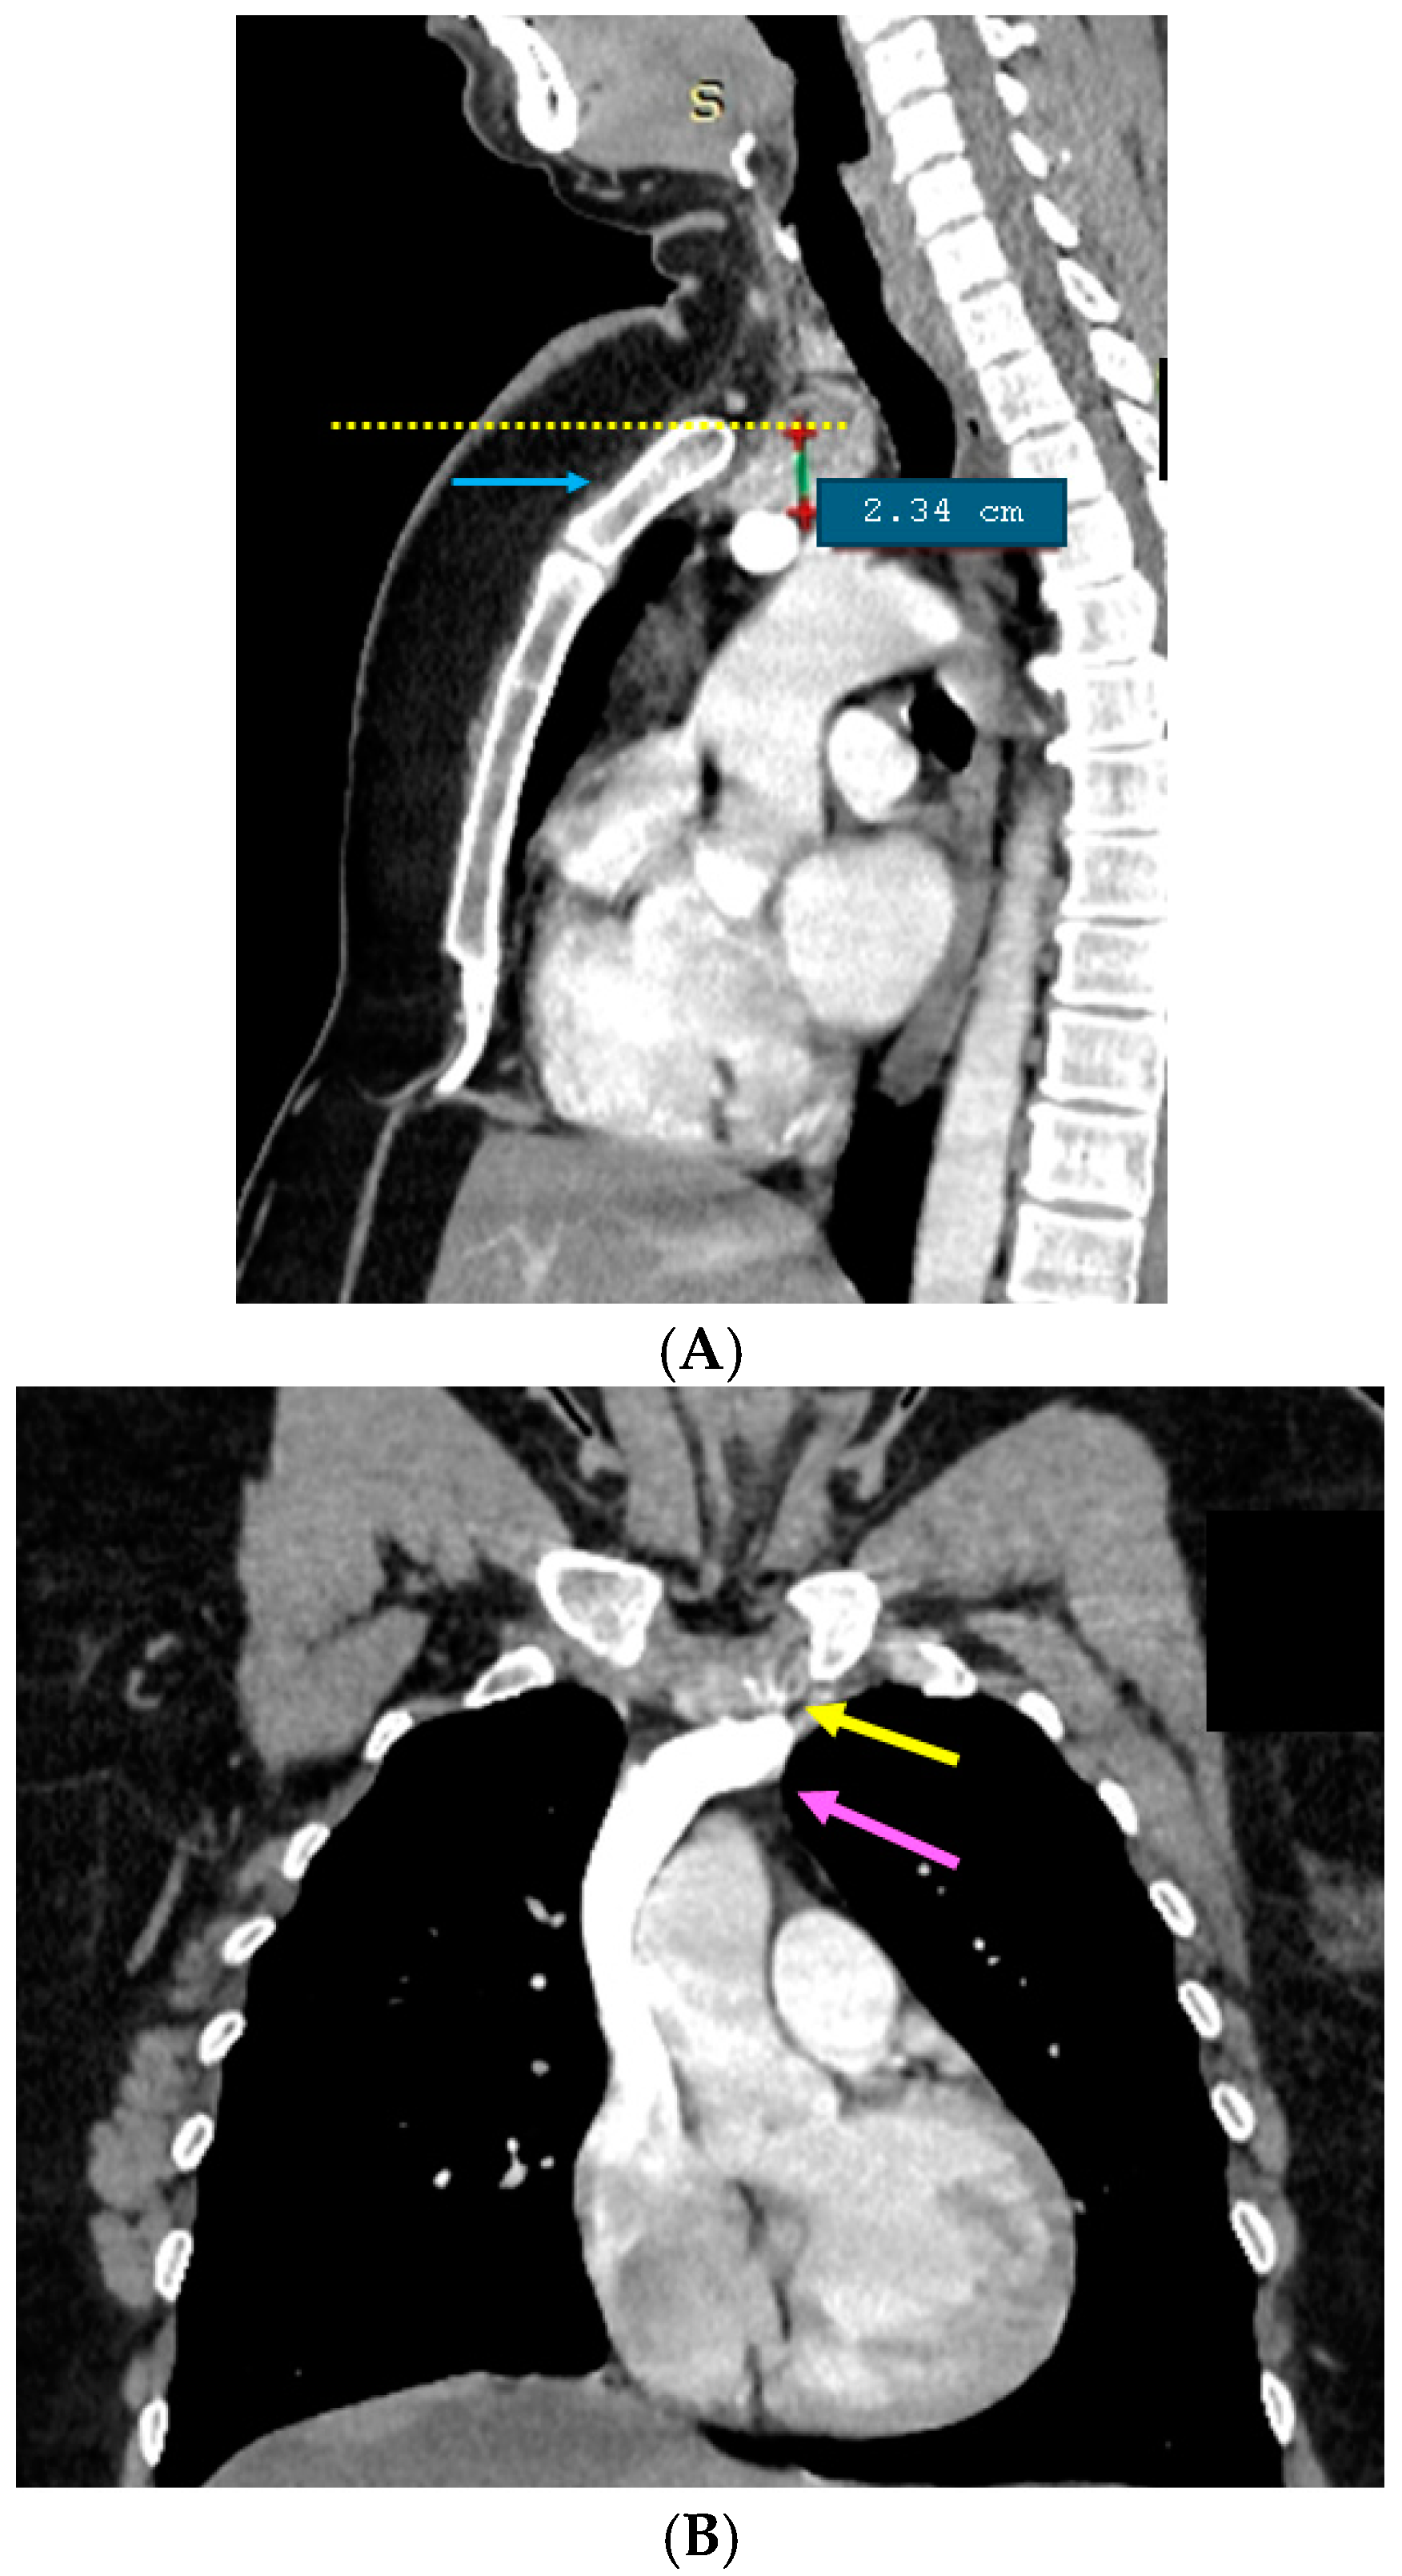

3.1.2. Endocrine and Imaging Investigations After One Year of Surveillance

- At the initial computed tomography, a small line of tissue was suspected to be the connective tissue between the orthotopic and ectopic thyroid, but it was not intra-operatory confirmed or after the post-surgery histological exam. This connective tissue facilitates the distinction between ectopic mediastinal tissue and a retrosternal extension of a cervical goitre [79];